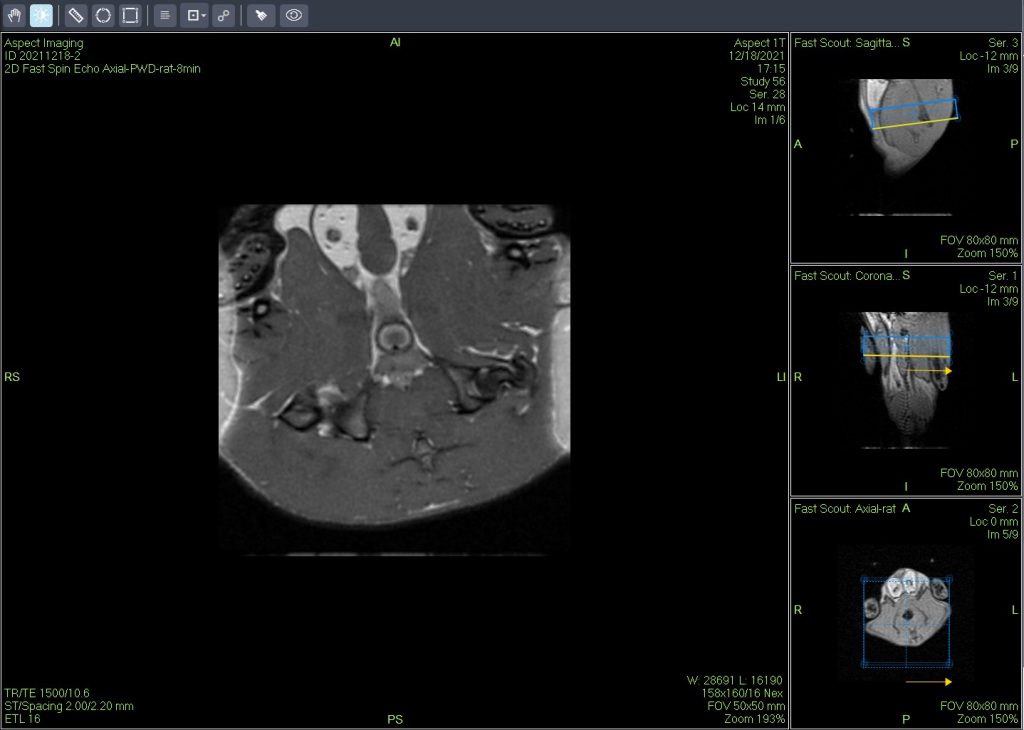

The Dixon fat suppression technique, originally proposed by Dixon, is based on the chemical shift difference between water and fat protons.By using different echo times, it acquires two sets of signals: one where water and fat protons are in phase, and another where they are opposed in phase.This enables the effective separation of water and fat signals in magnetic resonance imaging.